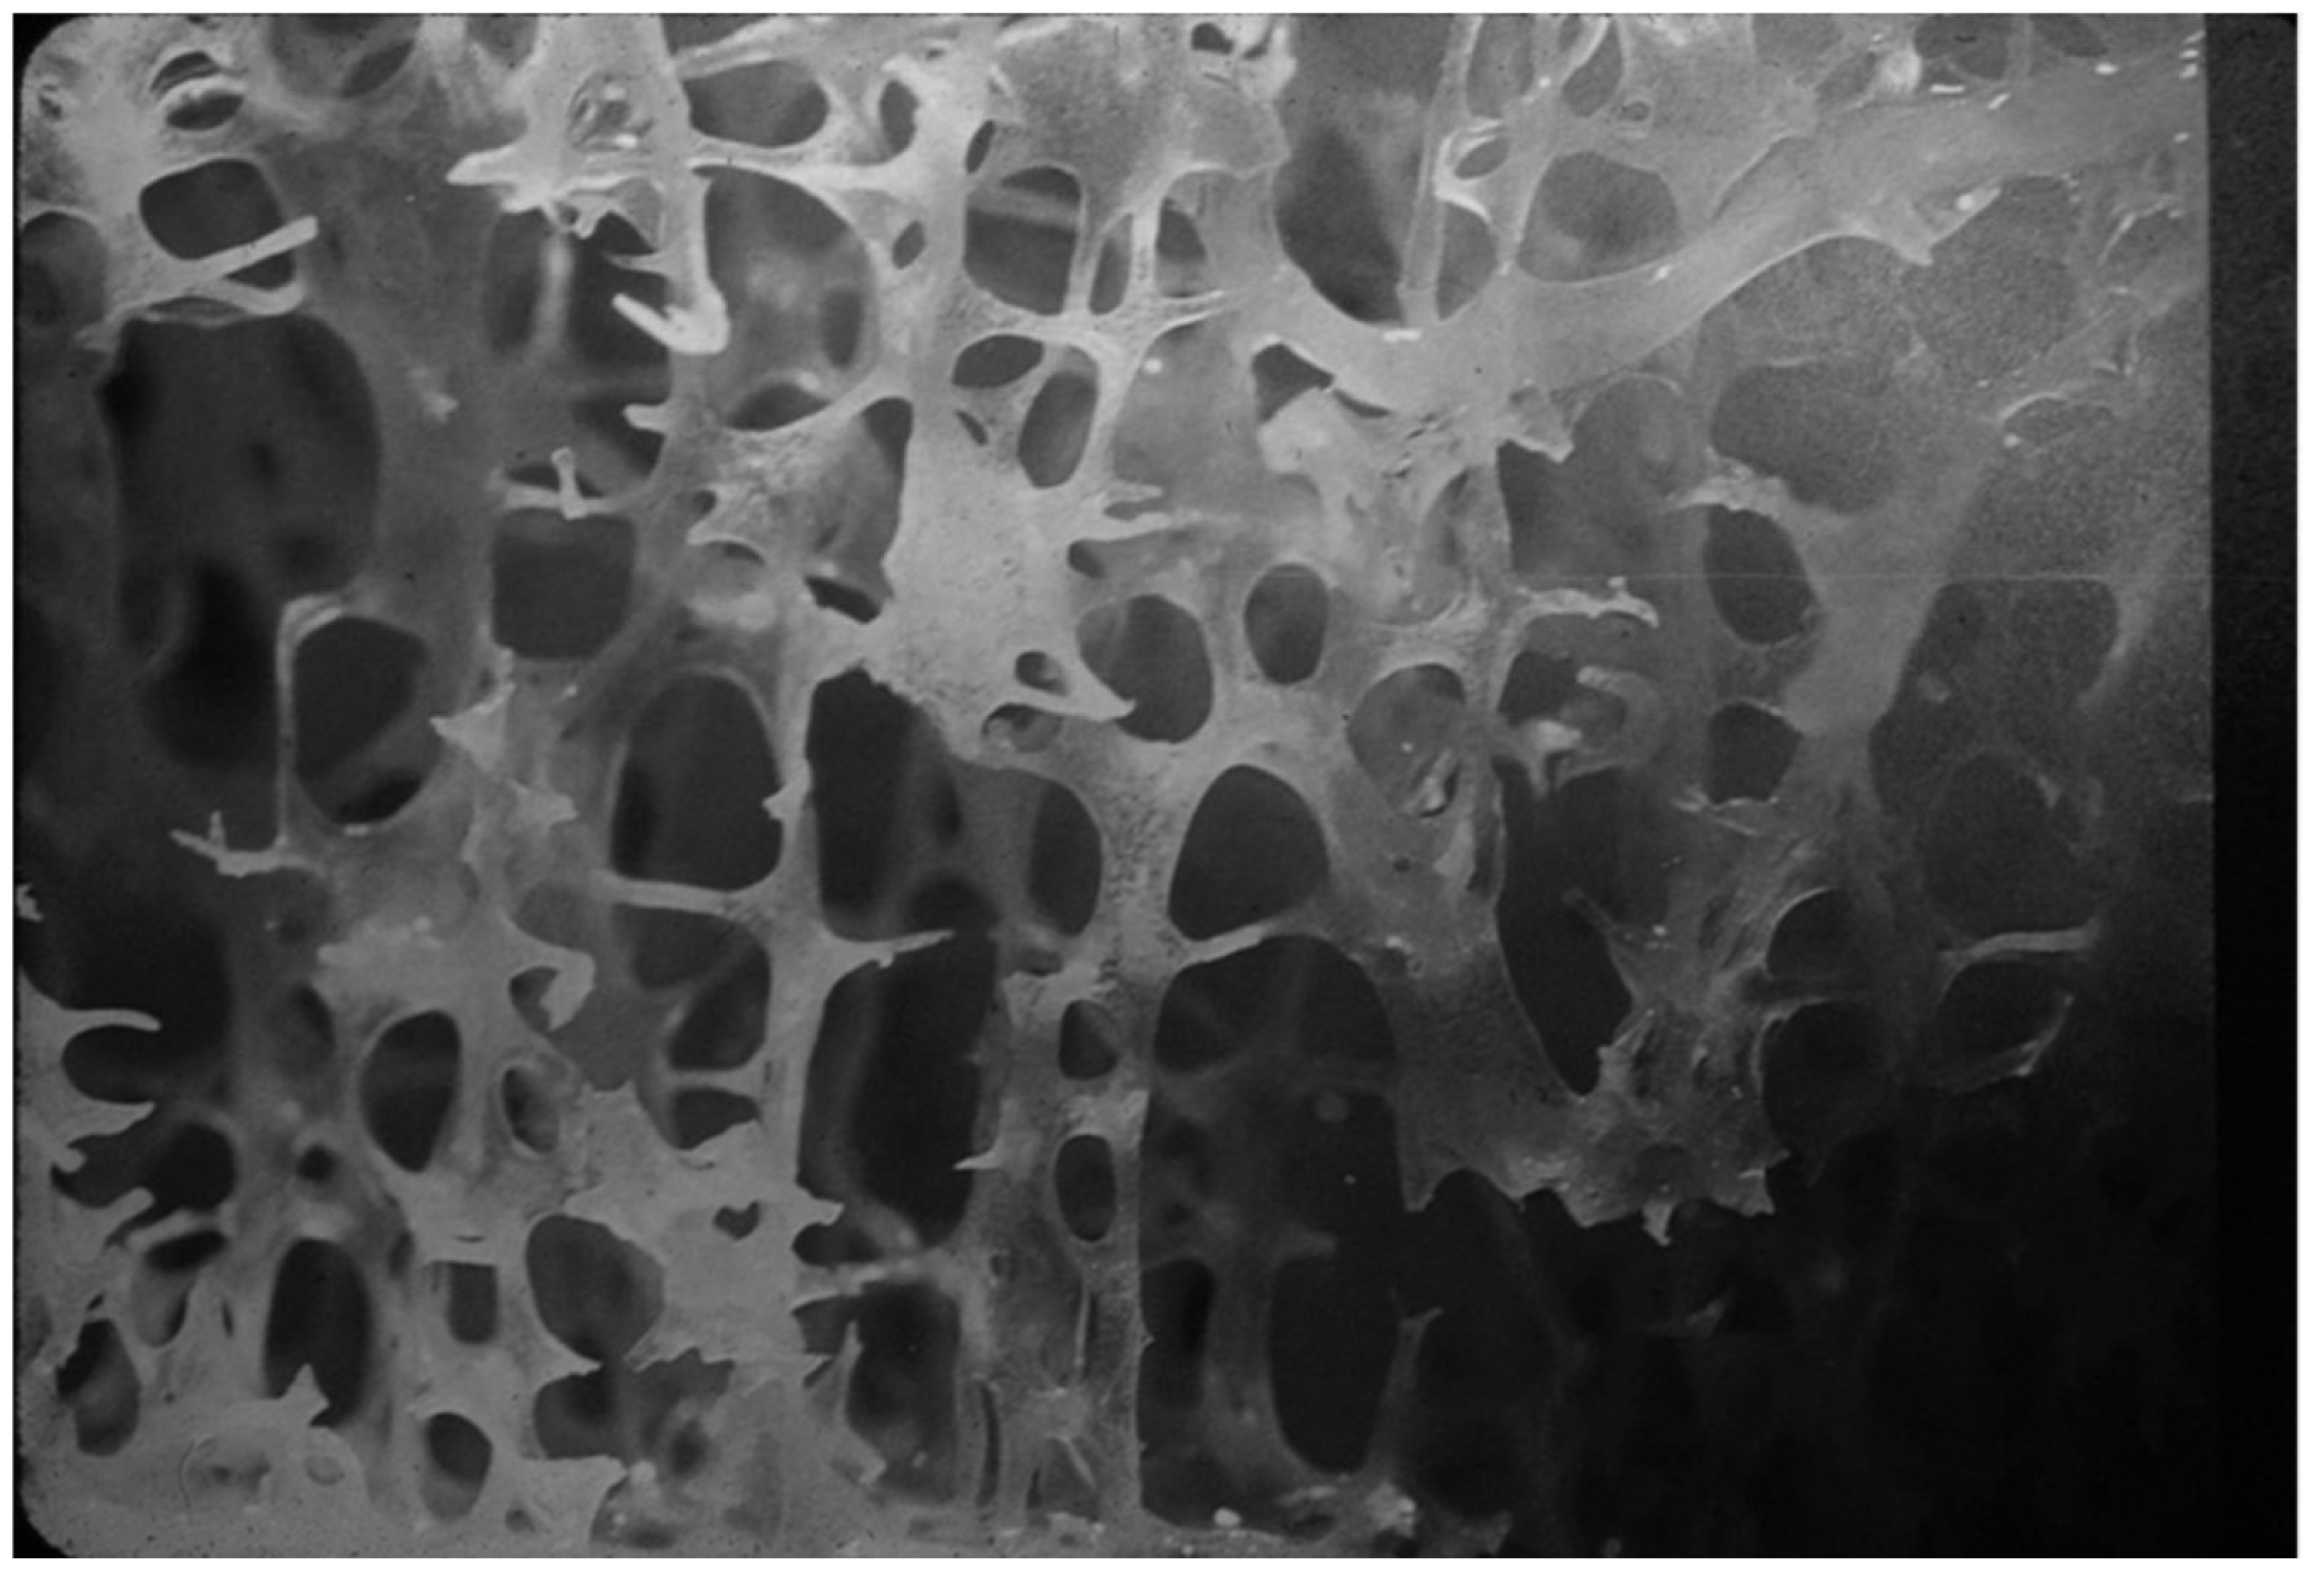

4.1.2. Levels of Bone Organization—Microarchitecture

4.1.3. Levels of Bone Organization—Cortex

4.2. Bone Pathology of Fibrous Dysplasia